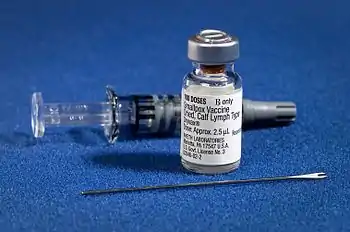

1 January 1967: Start of WHO intensified eradication campaign for smallpox (vaccination kit pictured)